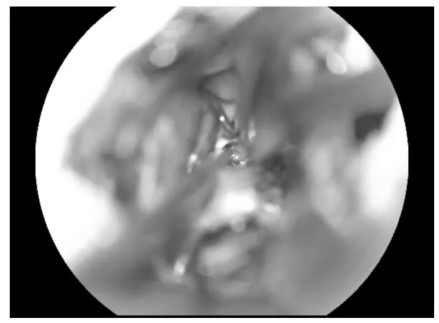

▼充分游離后組顱神經(jīng)與絨球

充分游離后組顱神經(jīng)與絨球

▼逐步暴露椎動(dòng)脈、PICA及延髓側(cè)方

逐步暴露椎動(dòng)脈、PICA及延髓側(cè)方

▼分離延髓表面血管

分離延髓表面血管

▼從后組顱神經(jīng)與PICA之間進(jìn)入延髓側(cè)方

從后組顱神經(jīng)與PICA之間進(jìn)入延髓側(cè)方

▼可見(jiàn)黃染的含鐵血黃素沉積帶

可見(jiàn)黃染的含鐵血黃素沉積帶

▼可見(jiàn)粗大的引流靜脈,予以保護(hù)

可見(jiàn)粗大的引流靜脈,予以保護(hù)

▼沿周邊黃染的含鐵血黃素沉積帶分離腫瘤

沿周邊黃染的含鐵血黃素沉積帶分離腫瘤

▼腫瘤標(biāo)本完整取出

腫瘤標(biāo)本完整取出

▼瘤腔止血

瘤腔止血

▼袖珍的延髓表面造痿口

袖珍的延髓表面造痿口

▼水密縫合硬腦膜

水密縫合硬腦膜

示范手術(shù)圓滿成功!困擾馮先生一年的延髓海綿狀血管瘤被完整切除,術(shù)后無(wú)任何神經(jīng)功能損傷。"沒(méi)有不舒服"——這個(gè)結(jié)果讓長(zhǎng)期飽受病痛折磨的馮先生喜出望外。更令人驚喜的是,術(shù)后第2天,巴教授查房時(shí)就用中文鼓勵(lì)他:"可以下床走走了,沒(méi)問(wèn)題!"看著教授自信的神情,馮先生露出了久違的笑容。此刻他確信,自己終于告別了這個(gè)可怕的疾病,迎接他的將是健康安穩(wěn)的新生活。